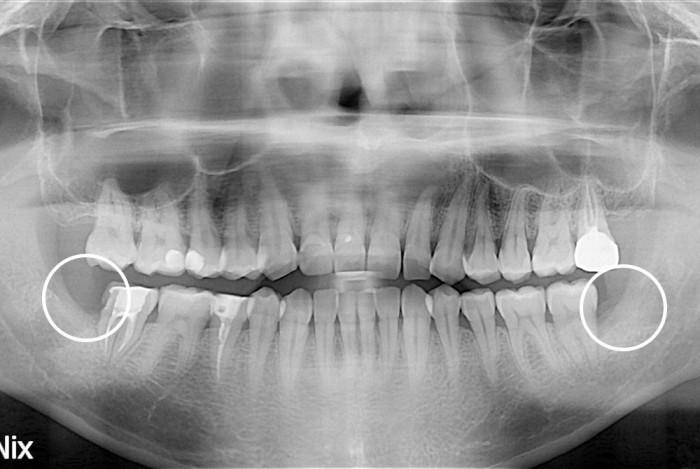

[사랑니] 사랑니

PX20200303_153857_0312_00000000.jpg

치료후 : 2020-03-03

세종치과는 구강악안면외과학 박사이신 원장님이 발치하는 치과입니다.